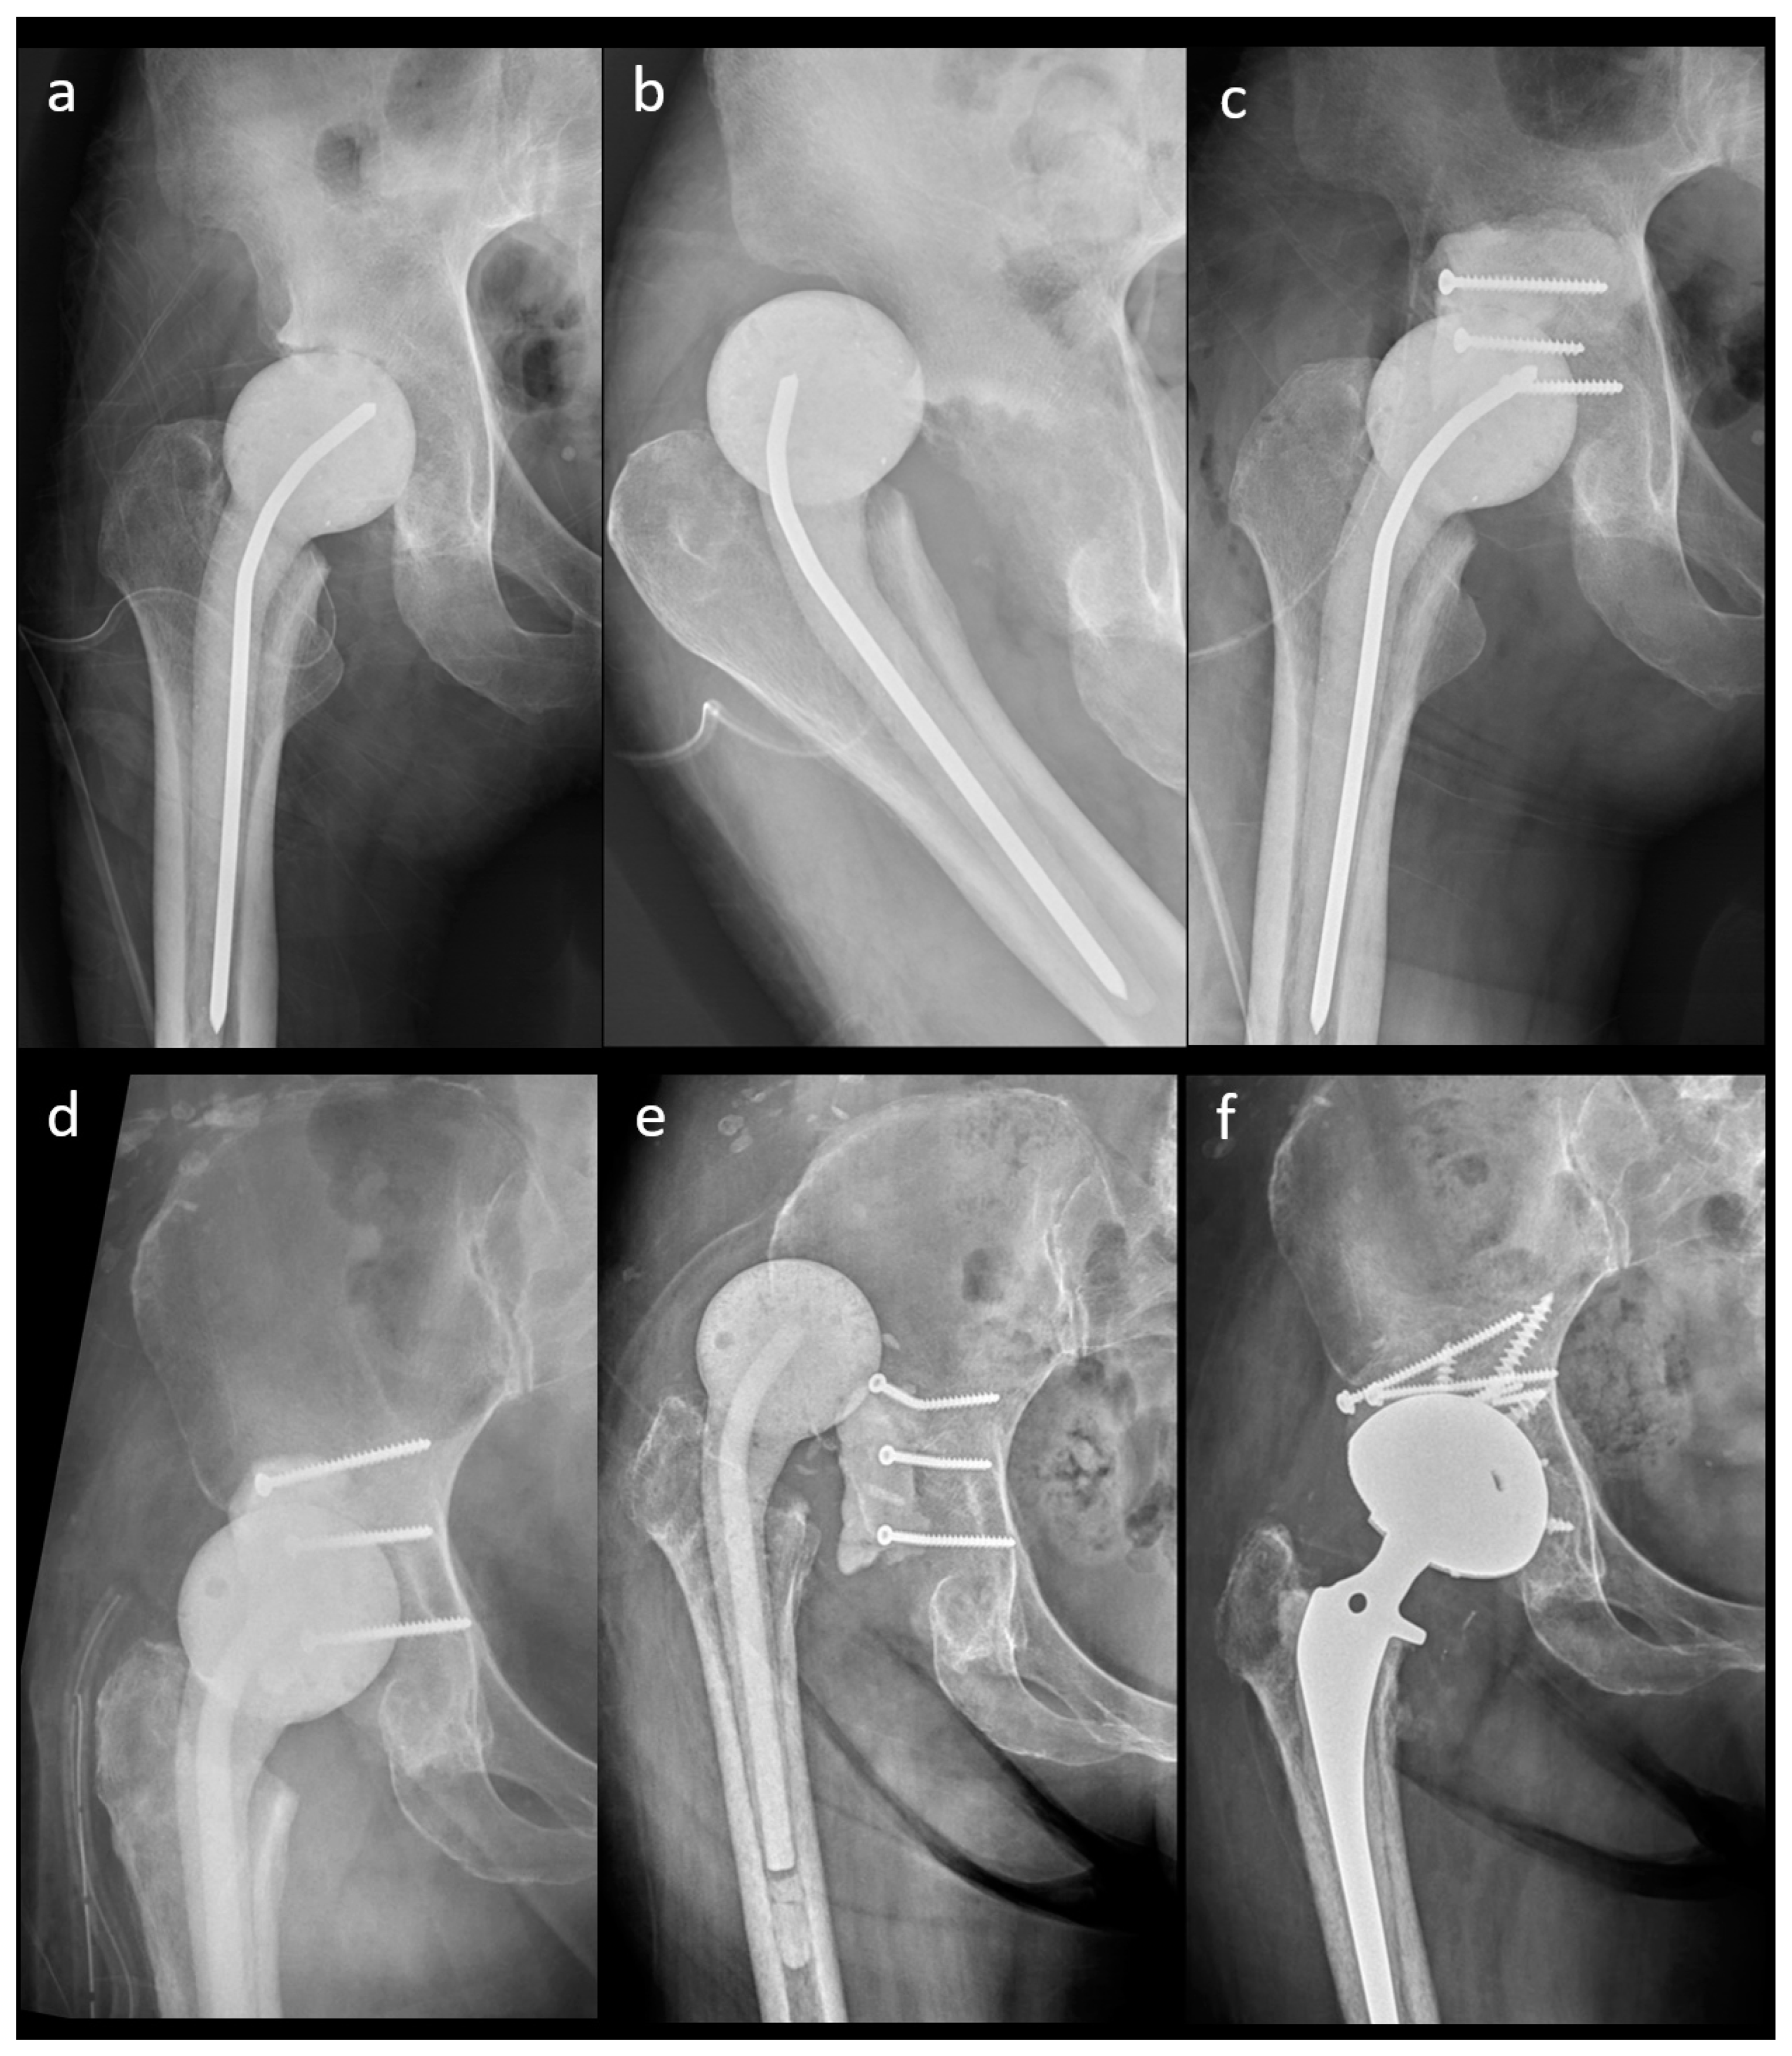

The outcomes of the n-MS and MS spacers are shown in Table 2. The intraclass correlation coefficient of spacer mechanical complications was 0.923 (range: 0.901–0.973, p < 0.001). The rate of spacer dislocation was significantly lower in MS (n = 0) than in n-MS (n = 10) spacers. The characteristics of joint dislocation were 100.0% nontraumatic posteriorly and 90.0% with early failure ≤3 weeks after n-MS spacer insertion (Table 3). Among 10 dislocated spacers, one underwent close reduction, four underwent open reduction with temporary cement tectoplasty (TCT) (Figure 5a–c), and four underwent spacer exchange with TCT. All patients were advised to use abduction braces after relocation and were free of dislocation. However, one underwent acute total hip arthroplasty (THA) without complications because of recurrent dislocation after 2 weeks of TCT (Figure 5d–f). Additionally, spacer retention was chosen for one patient because he was medically unfit for further surgery. One hip underwent permanent resection due to concomitant recurrent infection. The reoperation rate for spacer mechanical complications was significantly lower in MS than in n-MS spacers due to dislocated joints.

Figure 5.

A 41-year-old female patient with an n-MS spacer: (a) post-operative radiographs, (b) posterior dislocation 2 weeks after spacer insertion, and (c) open reduction combined with temporary cement tectoplasty. A 68-year-old male patient with an n-MS spacer: (d) open reduction combined with tectoplasty after posterior dislocation 4 weeks after spacer insertion, (e) recurrent dislocation after tectoplasty, and (f) acute reimplantation with bone grafting and cemented stem after the dislocation event and free of complications.